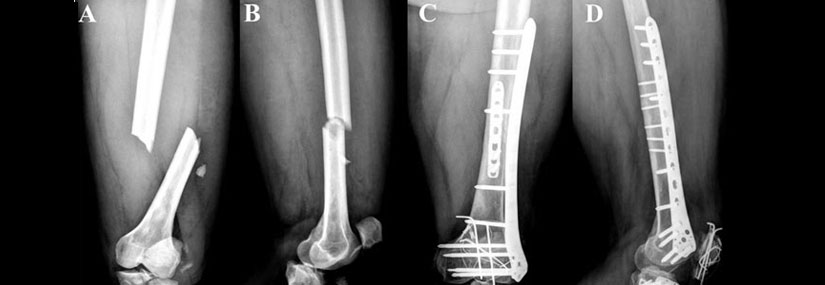

Tibia and Fibula (Leg Bones) Fracture:

• Types: Proximal (near the knee), mid-shaft, and distal (near the ankle) fractures.

• Causes: Direct impact, twisting injuries, falls.

• Symptoms: Severe pain, swelling, deformity, inability to bear weight.

• Surgery: Required for severe, displaced, or complex fractures. Surgical options include internal fixation with plates, screws, or rods, and in some cases, external fixation devices.